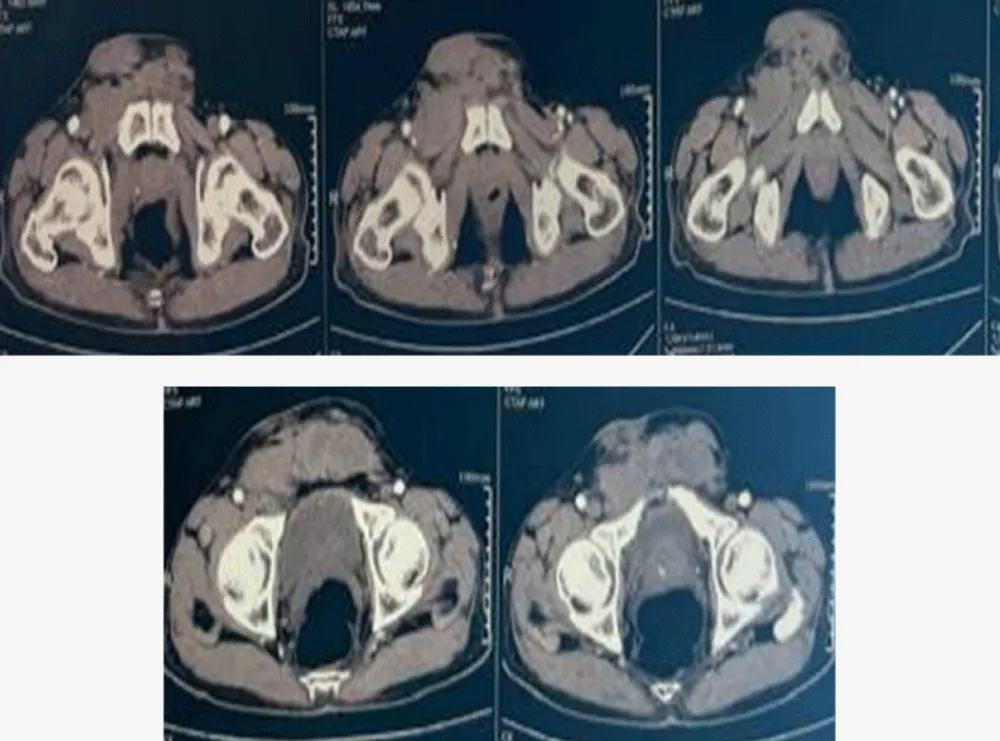

Computed tomography (CT) of the chest, abdomen, and pelvis performed in December 2025 (portal venous phase, 2.5 mm slice thickness) demonstrated extensive regional recurrence characterized by multiple infiltrating soft-tissue masses in the pubic region, including a 25×42 mm mass involving the right transverse abdominis muscle with infiltration of the ipsilateral pectineus muscle, a 34×72 mm mass infiltrating both rectus abdominis muscles, subcutaneous pubic masses measuring 49×26 mm on the right and 30×20 mm on the left, and right external iliac lymphadenopathy measuring 26×39 mm, without evidence of bone involvement, intraperitoneal spread, or pulmonary metastases (Figure 2).

Figure 2: Contrast-enhanced axial CT scan of the pelvis (portal phase, 2.5 mm slice thickness).

The imaging demonstrates extensive regional recurrence characterized by multiple infiltrating soft-tissue masses, including a 34×72 mm mass involving both rectus abdominis muscles and the right transverse abdominis muscle. There is notable involvement of the right external iliac lymph nodes (26×39 mm) and bilateral subcutaneous pubic masses, following the anatomical pathways of the initial surgical site and spermatic cord.